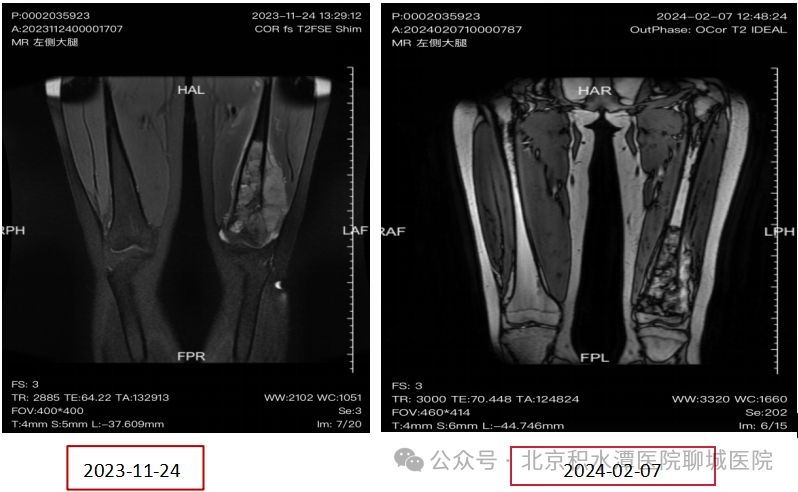

第三次化疗前后对比。

2024-02-07磁共振平扫+增强(左侧大腿):左侧股骨下段骨质内及邻近肌肉软组织占位,较前片2023-11-24范围略缩小。